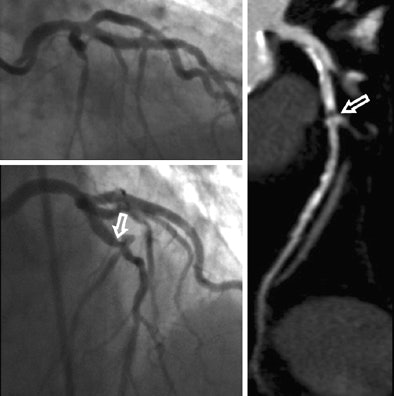

Coronary CTA found six segments and two patients with stenoses of 50% or greater that had been missed on initial angiography. The diagnostic accuracy between the tests was not significantly different (p = 0.87).

"Catheter angiography is a good gold standard, but it may not be the best because of limitations this test has which we all know about," Schoepf said. For one thing, angiography has trouble depicting a key coronary artery, the left main, because it's typically tortuous and complex anatomy is not well-suited to catheterization.

A current article in Circulation describes problems with the projection angles in catheter angiography, Schoepf said. Depending on the angle, a minor slit stenosis can appear quite significant at angiography, leading to false positives and potentially needless intervention.

"If you take vertical projection images of that it may look perfectly fine, but if you're angulated by 90°, you see a significant stenosis all of the sudden," he said.